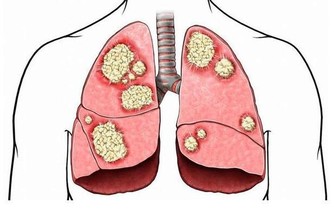

肝癌的凶險人人知之,它是我國常見的惡性腫瘤之一,死亡率很高,次於胃癌。

肝癌的發展,從第一個癌細胞在體內“誕生”開始,到患者身體出現明顯的不適,是非常漫長的一個過程。而在這漫長的過程裡,絕大部分的肝癌患者都不會出現異常,只有極少數患者可能出現食慾降低、上腹脹悶、腹痛等異常。

此外,在其他腫瘤比如賁門癌、胃癌、胰腺癌、膽管癌等中晚期,也可能會出現連續性打嗝的症狀,原因基本和肝癌相同,也不得不警惕。